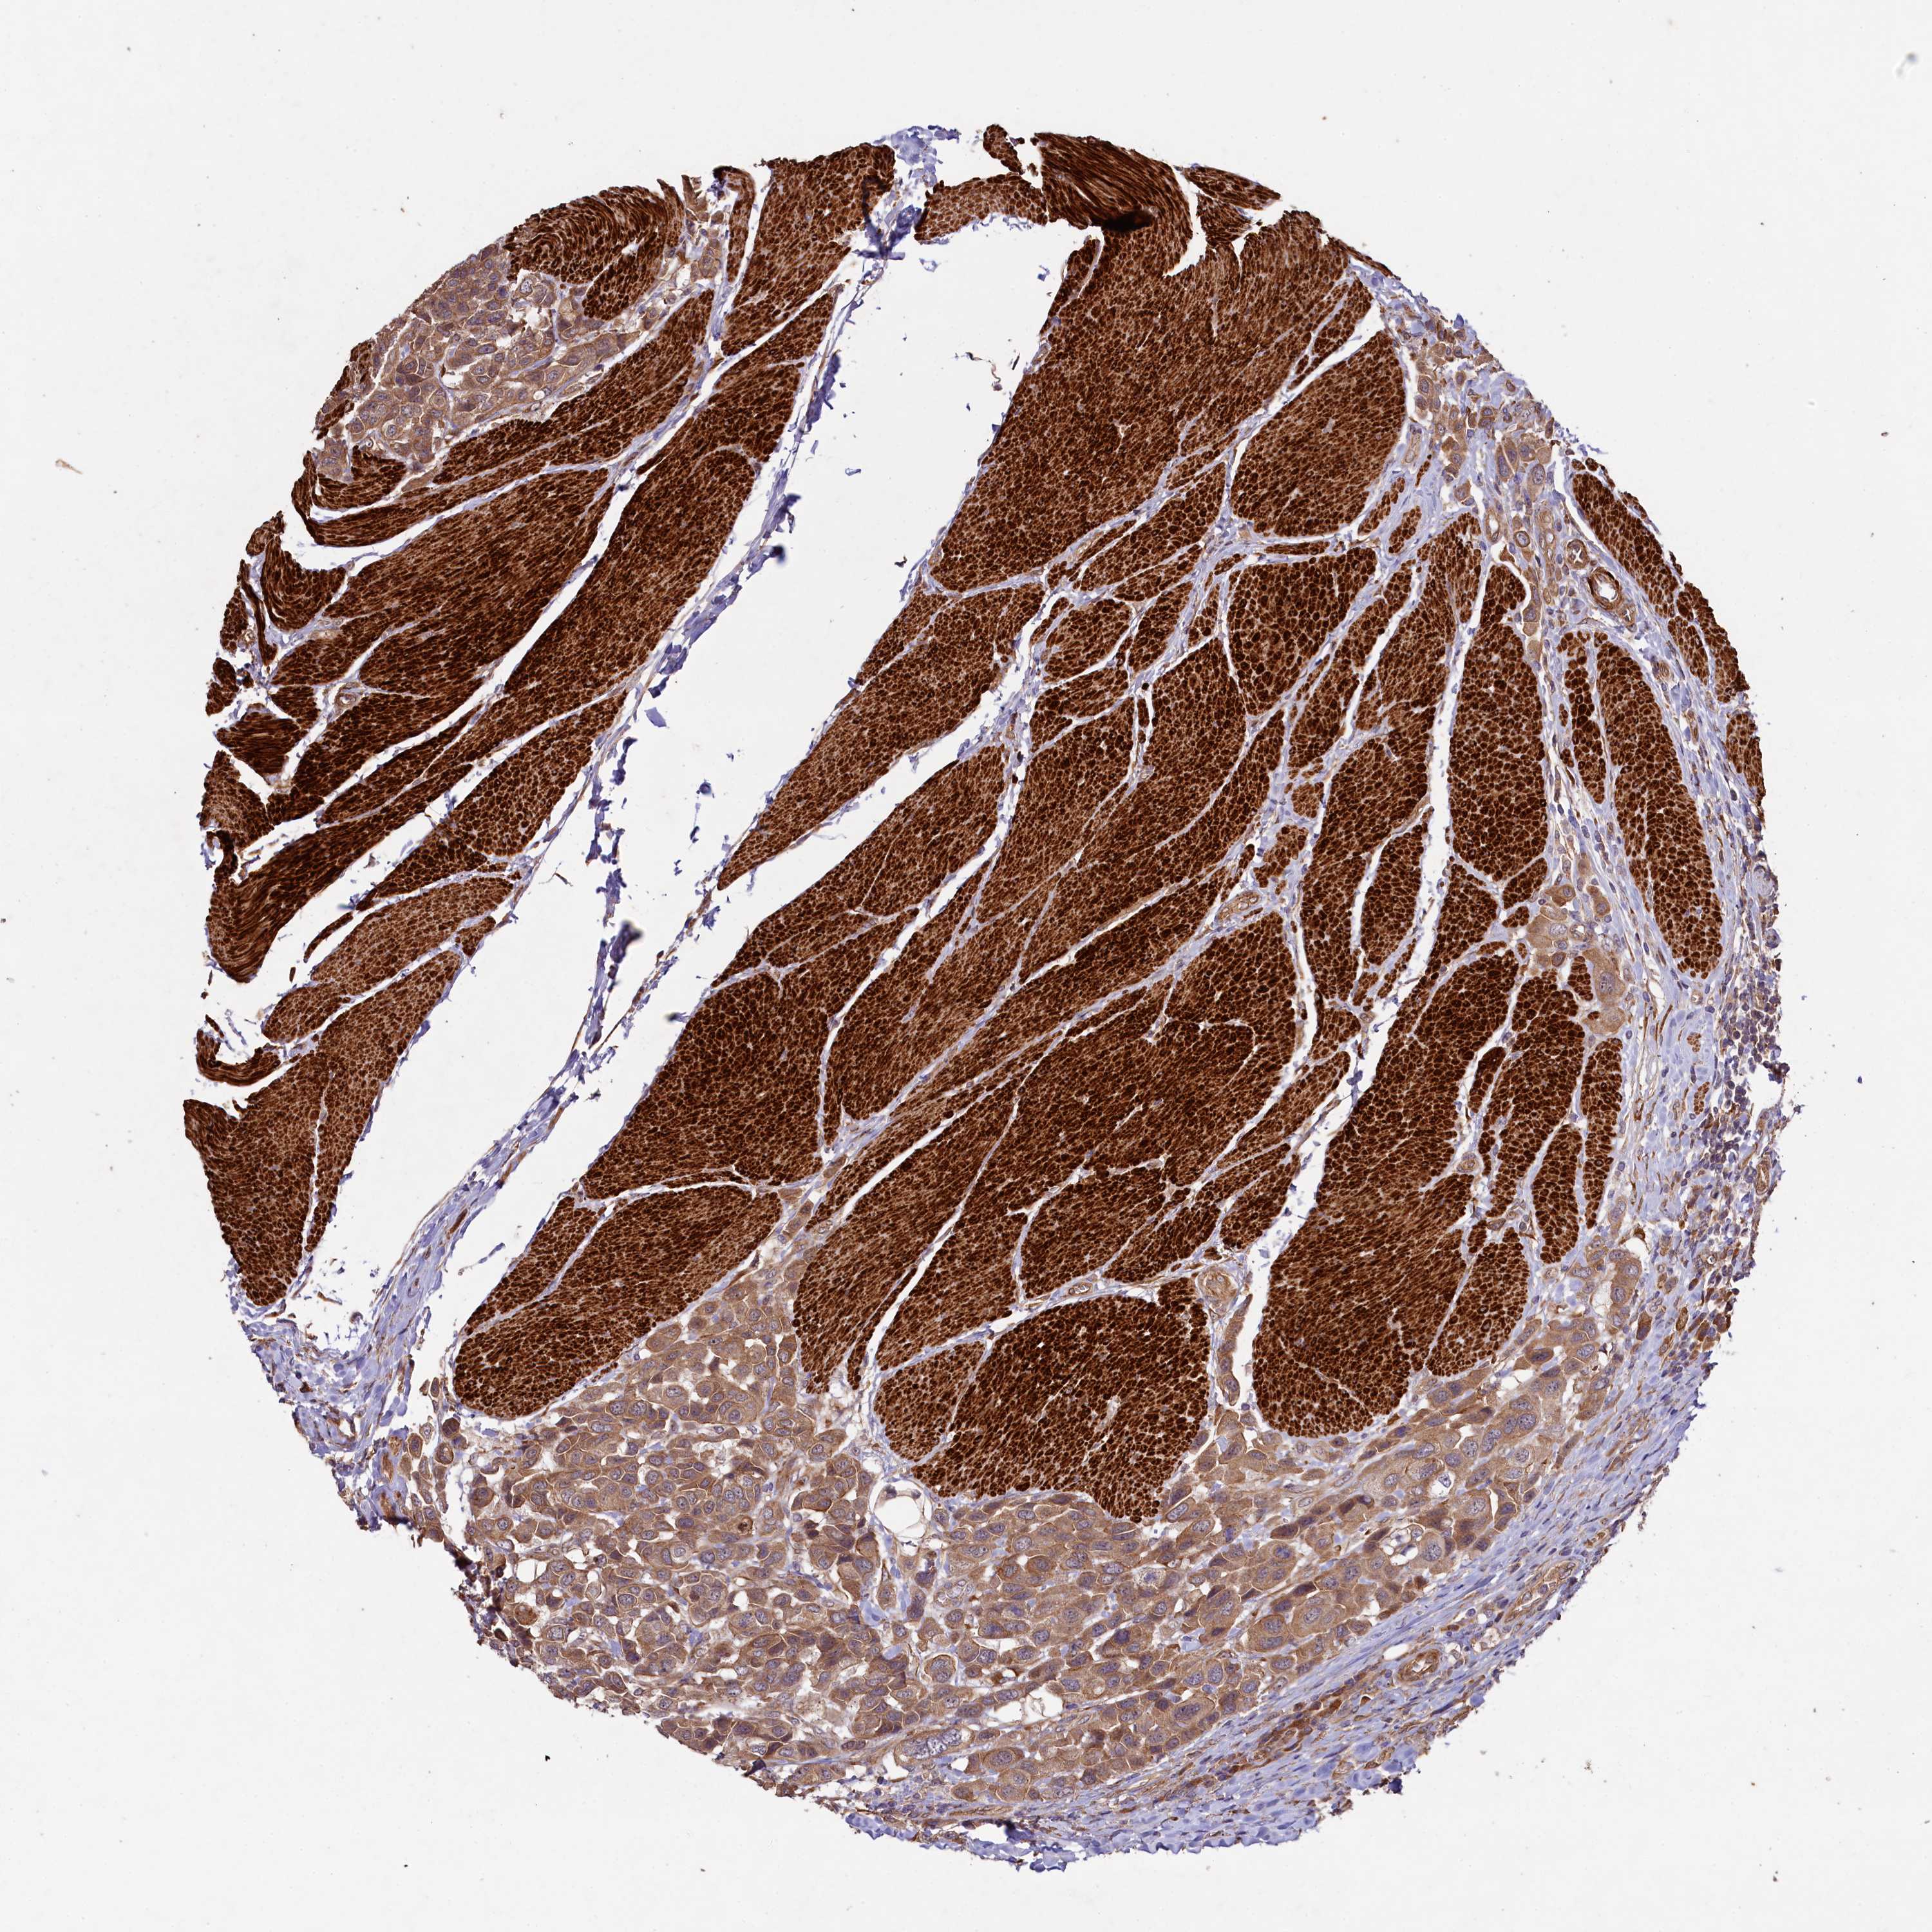

UROTHELIAL CANCER - Protein expressioni

A mouse-over function shows sample information and annotation data. Click on an image to view it in a full screen mode. Samples can be filtered based on level of antibody staining by selecting one or several of the following categories: high, medium, low and not detected. The assay and annotation is described here.

Note that samples used for immunohistochemistry by the Human Protein Atlas do not correspond to samples in the TCGA dataset.

Antibody stainingi

Antibody staining in the annotated cell types in the current human tissue is reported as not detected, low, medium, or high, based on conventional immunohistochemistry profiling in selected tissues. This score is based on the combination of the staining intensity and fraction of stained cells.

Each image is clickable and will lead to virtual microscopy that enables deeper exploration of all samples and also displays staining intensity scores, fraction scores and subcellular localization as well as patient and tissue information for each sample.

Antibody HPA040598

Antibody HPA040958

Staining

High

Medium

Low

Not detected

Intensity

Strong

Moderate

Weak

Negative

Quantity

>75%

75%-25%

<25%

None

Location

Nuclear

Cytoplasmic/membranous

Cytoplasmic/membranous,nuclear

Urothelial carcinoma, High grade

Urothelial carcinoma, Low grade